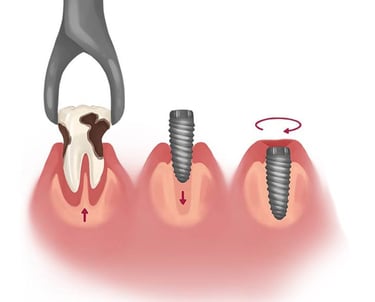

Se colocan implantes inmediatamente después de la extracción dental, reduciendo el tiempo total del tratamiento y manteniendo la estructura ósea.

Colocación de implantes inmediatos post-extracción

Consiste en insertar un tornillo de titanio en el hueso de la mandíbula o el maxilar, que actúa como raíz del diente y sirve de soporte para una corona, puente o prótesis dental.

Implantes Dentales